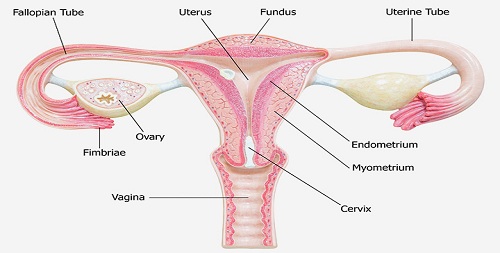

Uterine Nodule

Description. Uterine myomas (also: uterine leiomyomas, uterine fibroids) are an accumulation of numerous benign,..

Infertility

Infertility is quite common, affecting about 15 percent of couples, according to the National Library of Medicine...